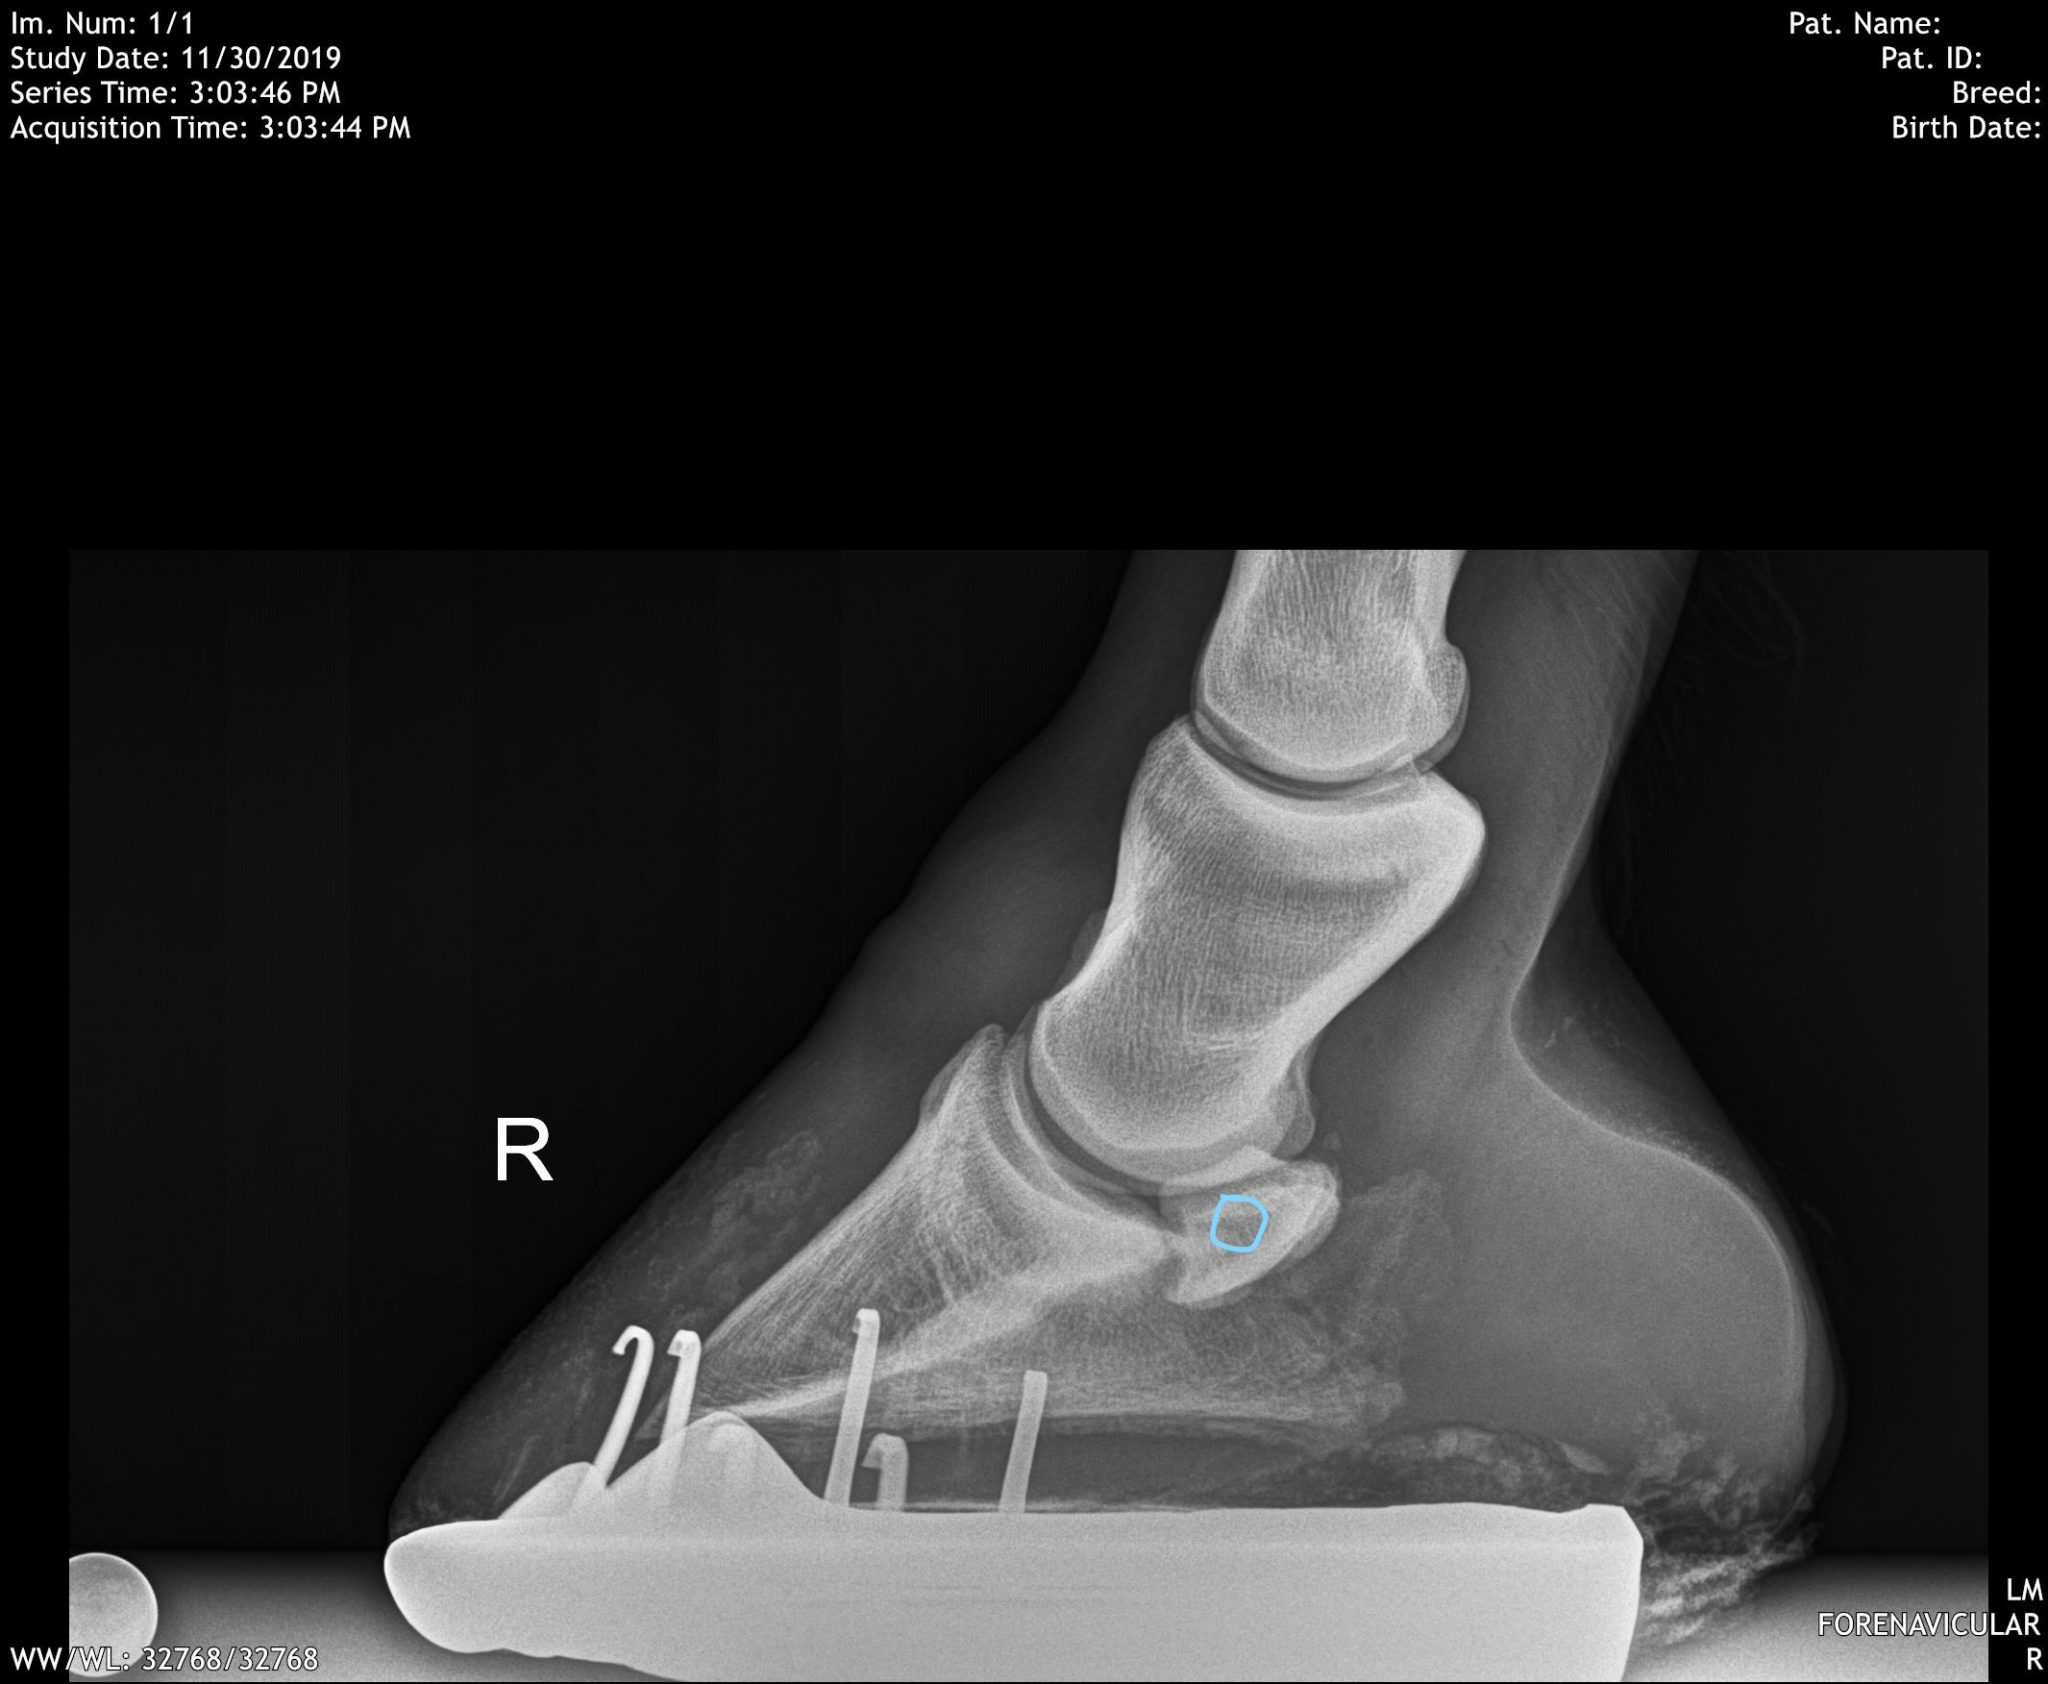

From swiftsureequine.com

December Navicular Cyst Swiftsure Equine Equine Navicular Bursa Injections The significance of a positive response to analgesia of the navicular bursa has not been established. Following diagnostic imaging, injection of the navicular bursa may be indicated. Needle placement for treatment of the navicular. Injection of the navicular bursa is commonly performed from the palmar aspect of the limb, which results in penetration of the deep digital flexor tendon (ddft).. Equine Navicular Bursa Injections.